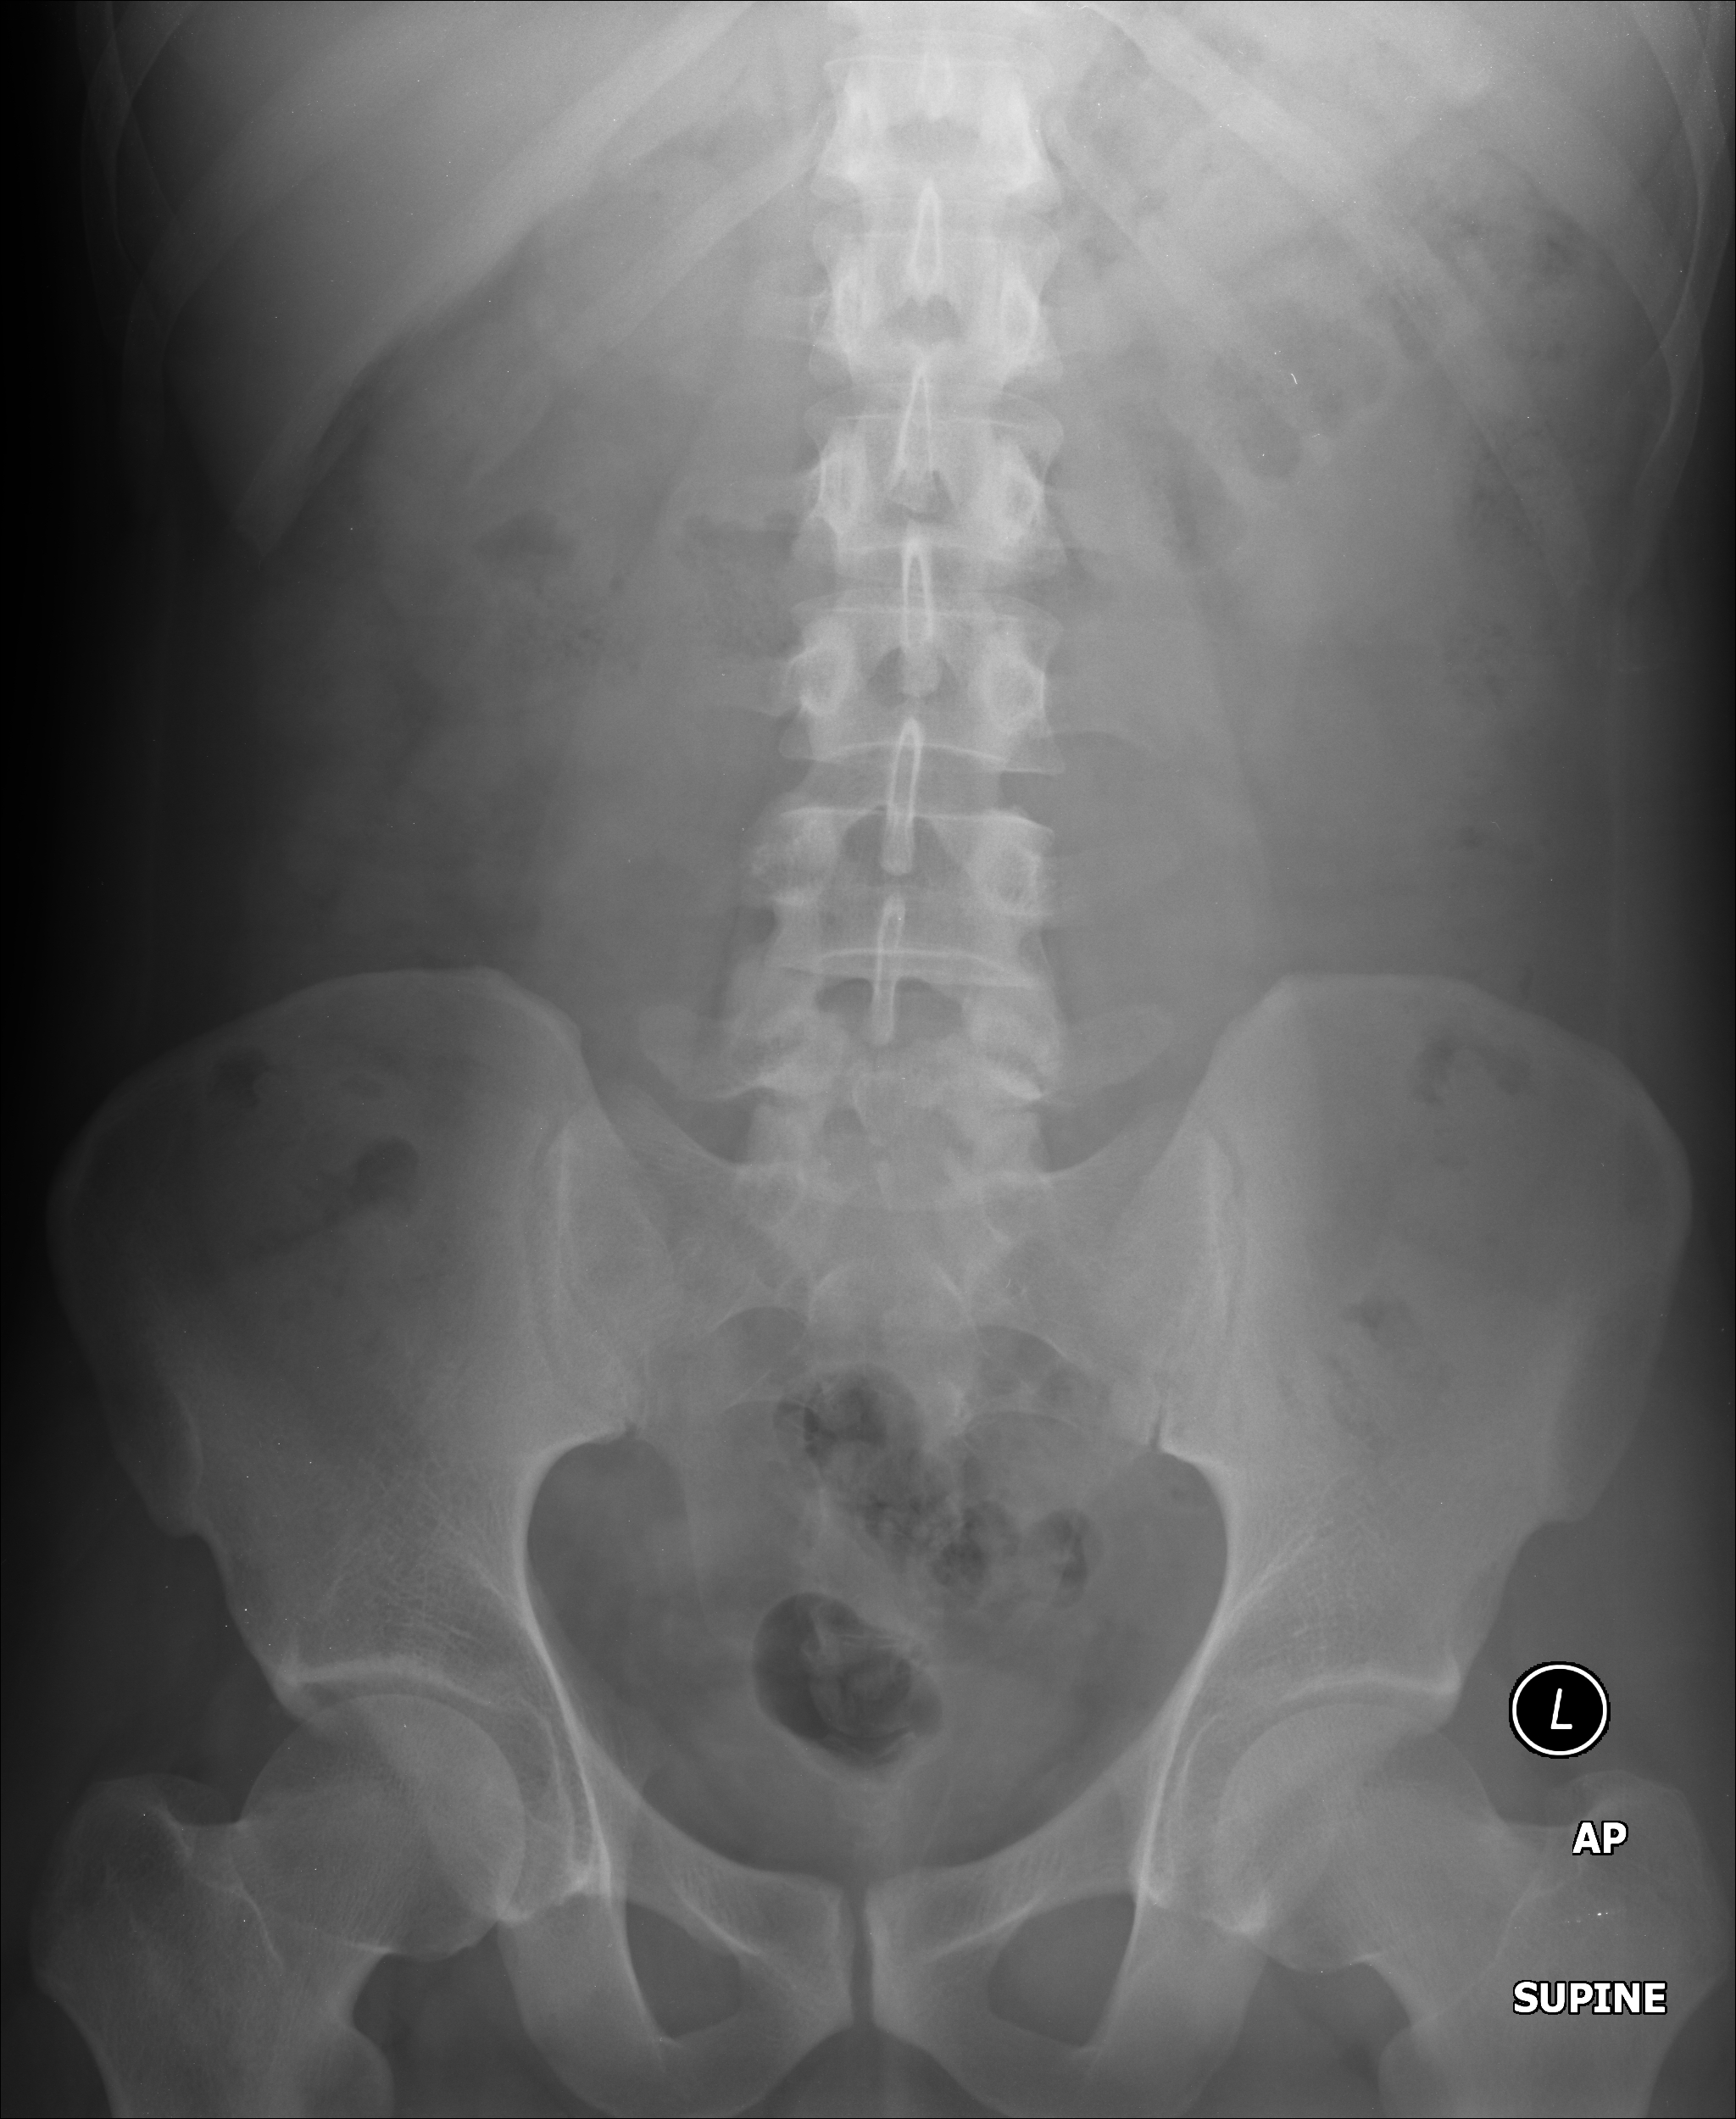

Рентген шейных позвонков при спина бифида

Раздел: Фотозарисовки